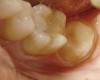

Preparation of tooth No. 18 was performed by the dentist with a 1.5-mm occlusal reduction and a 1-mm axial reduction with a 3° to 5° tapered shoulder margin. Crown build-up was directly restored with Clearfill SE Bond 2, Clearfill DC Activator from Kuraray (kuraraydental.com), and Danville Bulk-EZ shade A2 from Zest Dental Solutions (zestdent.com) (Figure 1). The full-arch mandibular impression and full-arch maxillary opposing impression were taken with 3M Imprint (3M, 3m.com), and the bite registration and intraoral images were provided by the dentist to the laboratory. Custom shading was acquired by the technician before the preparation of the tooth structure to avoid dehydration.

Fig 1. Tooth No. 18 crown build-up was directly restored.

Figure 1